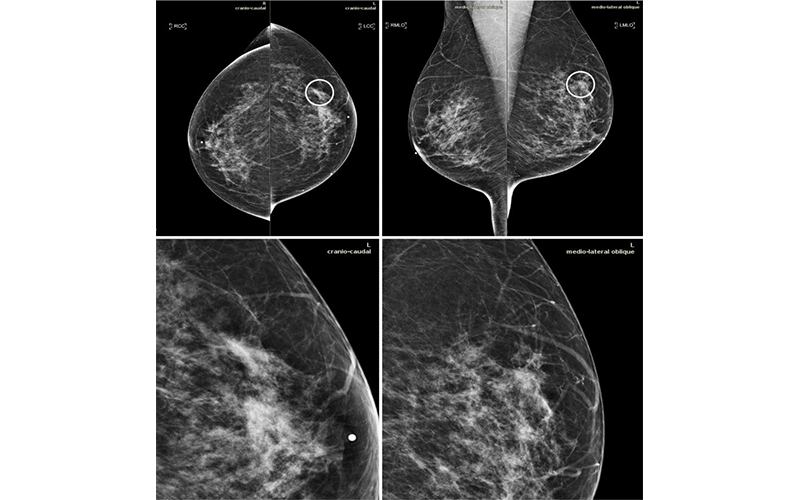

Mammograms in a 51-year-old woman with invasive ductal carcinoma. The upper panels show the craniocaudal and the mediolateral oblique views. The lower panels show a close-up of the left breast area containing the lesion. The case is one of the false-negative cases included in the dataset. Accordingly, the initial screening assessment was a BI-RADS 2, meaning visible findings were judged as benign. After 1 year, the patient presented for another screening examination. This time, a focal asymmetry with associated distortion within the left breast was noticed; the patient was recalled and diagnosed with a 1.5-cm mass in the upper outer quadrant of the left breast on the craniocaudal view (circle).